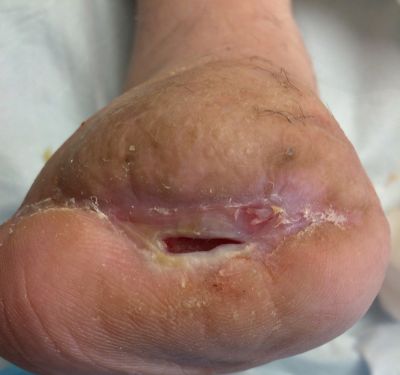

Assessment during her first visit to the clinic revealed trophic skin changes of chronic ischemia, and non-palpable dorsal pedis (DP) or posterior tibial (PT) pulses. Capillary refill was sluggish. The contralateral limb presented similarly. The periwound was boggy and mottled, and the wound bed was a dry, dull red. Bone from the first metatarsal was visible, but appeared viable. Both bone and tissue specimens were taken for PCR (polymerase chain reaction) plus culture and sensitivity, of which only the tissue revealed significant growth of pathogens; osteomyelitis was not suspected at this juncture. The patient's wound was covered with a moisture retentive dressing and she was immediately referred to the lower extremity vascular specialist at the neighboring heart institute, where she underwent successful, albeit complex, vascular intervention.

Within an 8 week period, she received targeted oral antimicrobial therapy and conservative wound care inclusive of sharp debridement, strict offloading, and dressings to promote moisture and healthy tissue proliferation in the wound bed. The patient-centered plan also included glucose control, dietary modification to include protein supplementation, and smoking cessation. Despite all the above measures, the wound continued to probe to bone, and showed little signs of healing.